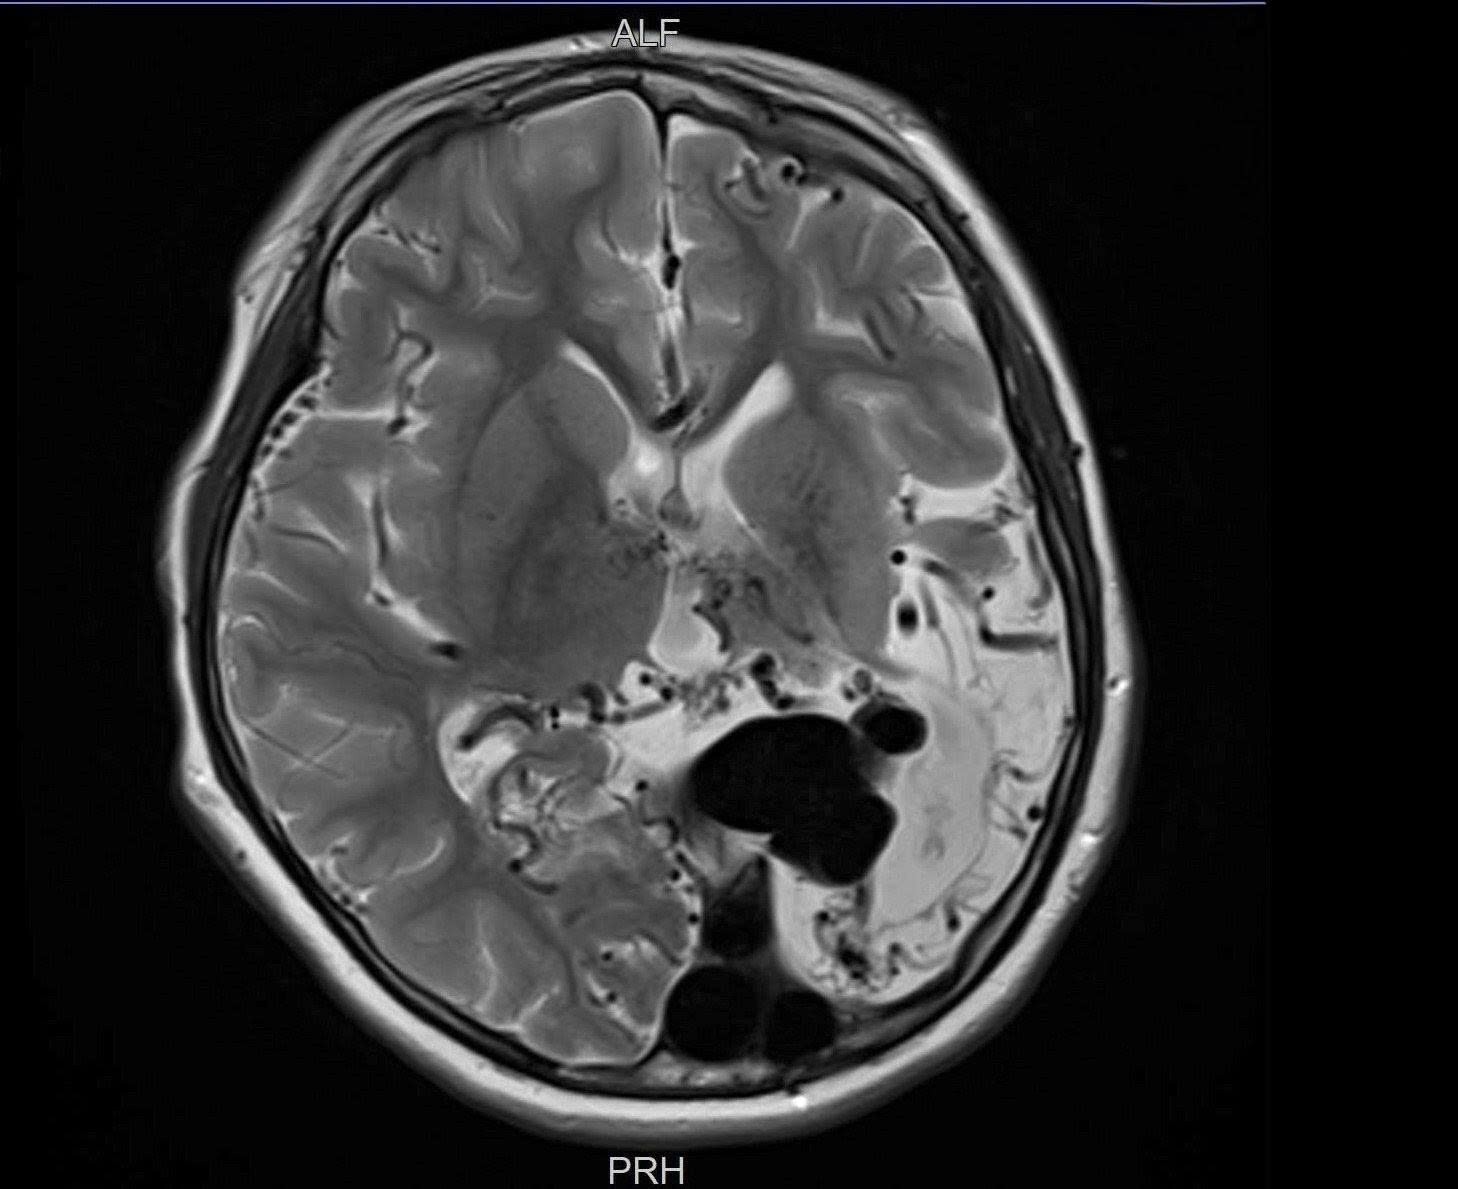

Hình chụp MRI não cho thấy khối dị dạng đã chiếm một vùng não của bé